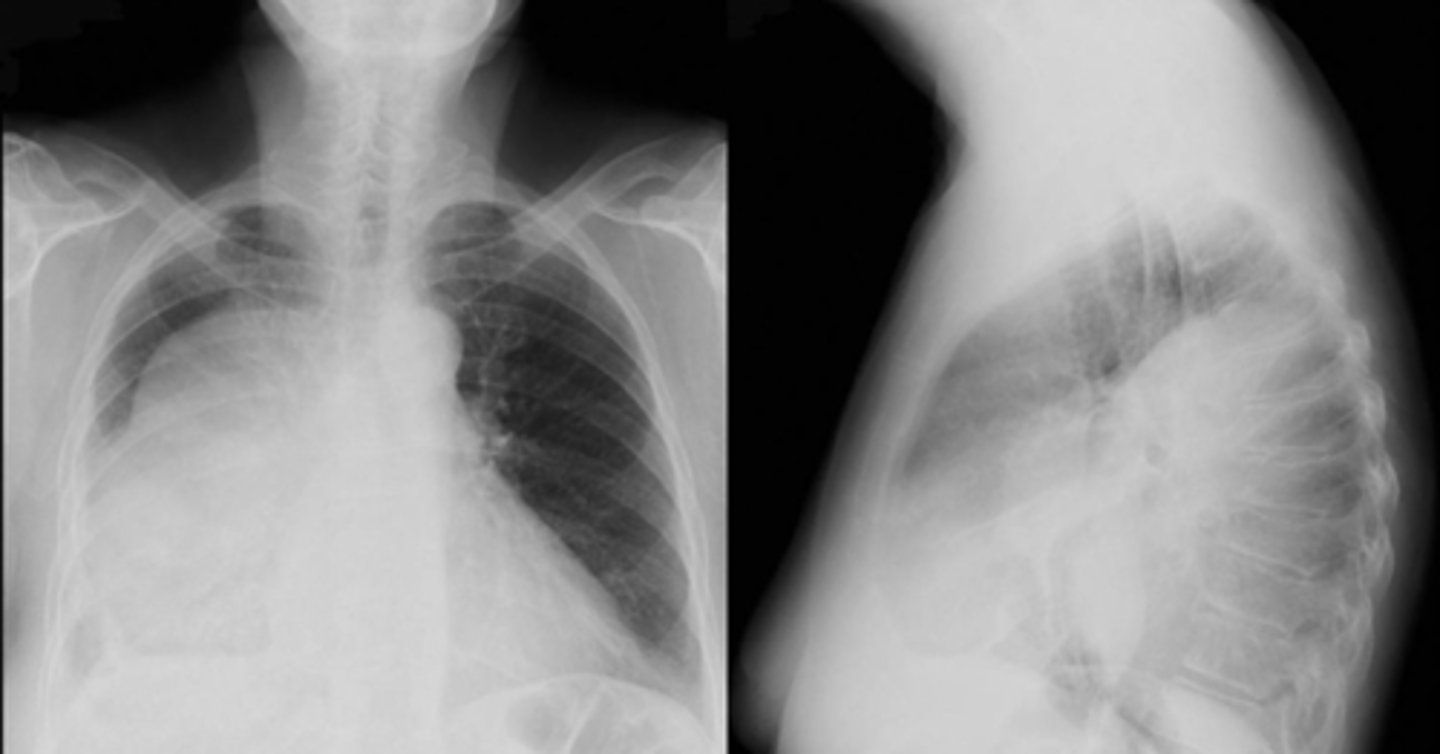

Tension pneumothorax

knowt flashcard image

Tension pneumothorax (right)